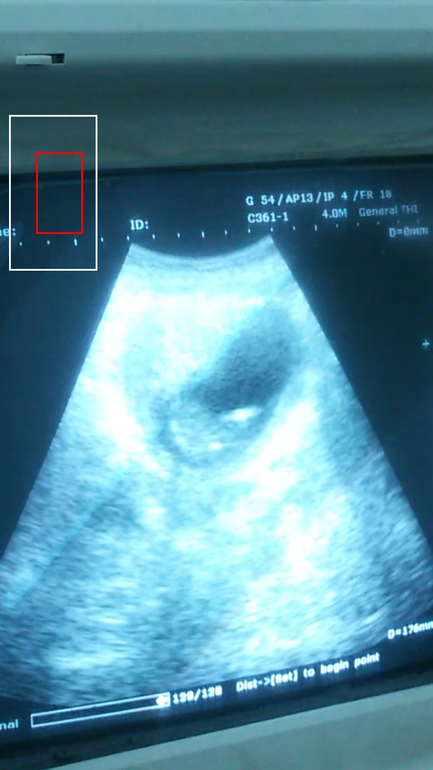

Вот мой ляль, не маловат как думаете, успеваем? Аппарат тоже был не очень, в общем не знаю разглядите ли чего

Вам выдали заключение? Там должно быть написано CRL- он же КТР. И GA 13w1d - он же акушерский срок. На самом УЗИ, когда замеры делают, в правом нижнем углу обычно пишутся эти показатели. По вашей фотографии не понятно...

Малыш соответствует 10+5 акушерским неделям. А по месячным у вас, я так понимаю, 15+4. Вообще отставание в 5 недель это много... Но если ребенок растет, движется, сердечко бьется, может вы неправильно считаете дату зачатия/овуляции/последних месячных?

По месячным у вас должно быть почти 14 недель. По УЗИ поставили почти 11. А цикл у вас длинный? Овуляция когда была знаете?

хм...странное узи,если честно....наверное аппарат такой..а что про малыша говорят???????если судить по фотке,то у нас малыш так выглядел в 7нед+6дн

Не не уж точно не 7 нелель)))) Просто то что я паказала фото это отрывок из видео, на самом леле видно что крупнее. Просто в россии на новых аппаратах ручки нодки все видно а тут пятно одно и все... ((